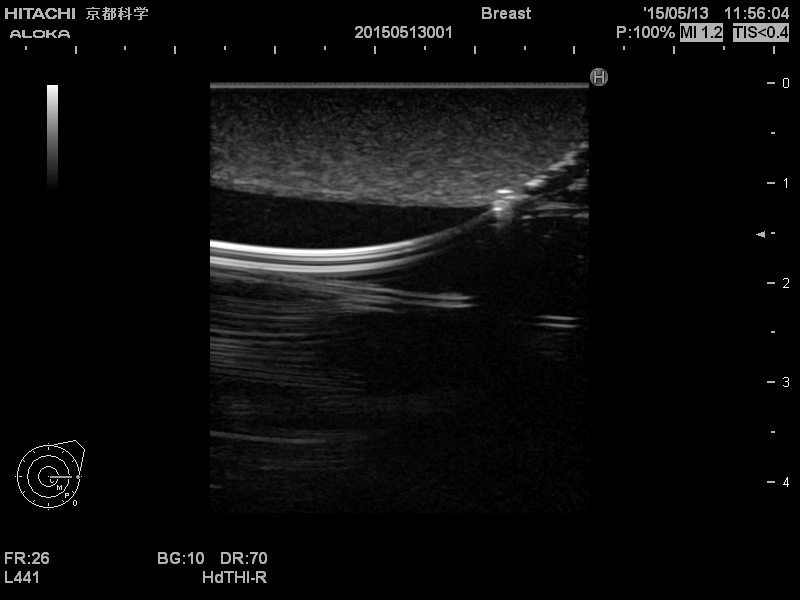

Simulator für die zentrale Venenpunktion LM90

Ausgelegt für das Üben der ultraschallgesteuerten zentralen Venenpunktion und der Punktion anhand anatomischer Strukturen. Ermöglicht den Lernenden, die Punktionsstelle durch Erkennen der wichtigen anatomischen Landmarken zu ermitteln.

Durch Einführen einer Nadel in die Venen kann Kunstblut entnommen werden. Die Lernenden können eine zentrale Venenpunktion durchführen, indem sie einen Unterdruck in der Spritze erzeugen. Rückströmender Luftdruck zeigt eine fehlerhafte Punktur der Lunge an. Diese Übungsvorrichtung wurde für das Üben von Punktionen ausgelegt. Katheter und Führungsdraht können nicht eingesetzt werden. Eine zentrale Venenpunktion mit Hilfe eines Ultraschall-Geräts ermöglicht das Üben der Punktion der inneren Drosselvene, der Punktion der Schlüsselbeinvene und die Punktion der Vene oberhalb des Schlüsselbeins. Druck auf die Vena jugularis interna durch die Ultraschallsonde verursacht eine ovale Verformung der Vene. Beachten Sie bitte, dass das Ultraschall-Gerät am Modell anders funktioniert als im menschlichen Körper. Deshalb können die Bilder, welche Sie mit dem Ultraschall-Gerät vom Modell erzeugen anders aussehen als beim Patienten.